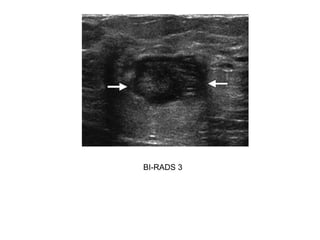

Case 1: BIRADS II lesion

BI-RADS 3